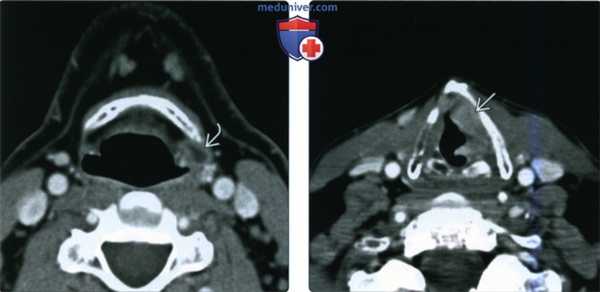

(Слева) При аксиальной КТ с КУ определяется жидкостное образование левой околоскладочной области. На этом срезе оно выглядит как внутреннее (простое) ларингоцеле.

(Справа) При аксиальной КТ с КУ на уровне истинных голосовых складок у этого же пациента определяется инфильтративное образование левой половины гортани, перекрывающее вход в гортанный желудочек и являющееся причиной вторичного ларингоцеле, показанного на предыдущем изображении. Примерно 75% всех ларингоцеле оказываются вторичными.